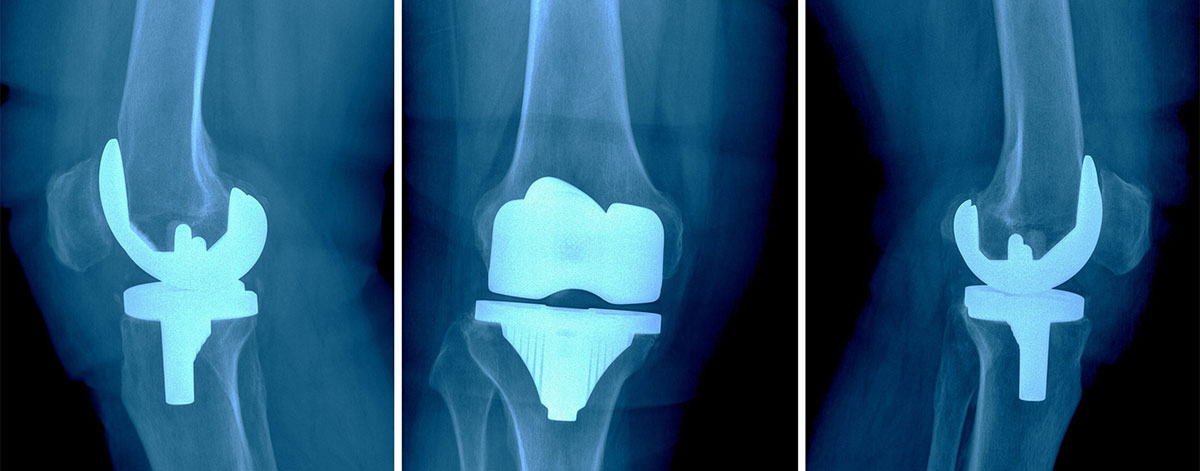

During the knee replacement surgery, the surgeon removes the damaged portions of the knee joint, including the ends of the femur (thigh bone) and tibia (shin bone), as well as any damaged cartilage in between. These are replaced with artificial components made of metal, plastic, or a combination of both. The prosthetic components are designed to replicate the natural movement and function of a healthy knee joint.

• Total Knee Replacement (TKR): In a total knee replacement, all three compartments of the knee joint are replaced - the medial compartment, lateral compartment, and patellofemoral compartment.

• Partial Knee Replacement (PKR): If the damage is limited to only one compartment of the knee joint, a partial knee replacement may be performed, where only the damaged compartment is replaced.